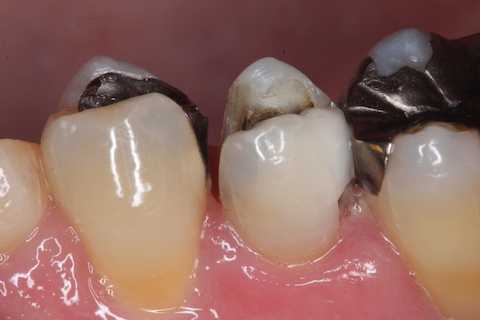

今日の充填治療55(遠心隣接面カリエス) 2023.12.21